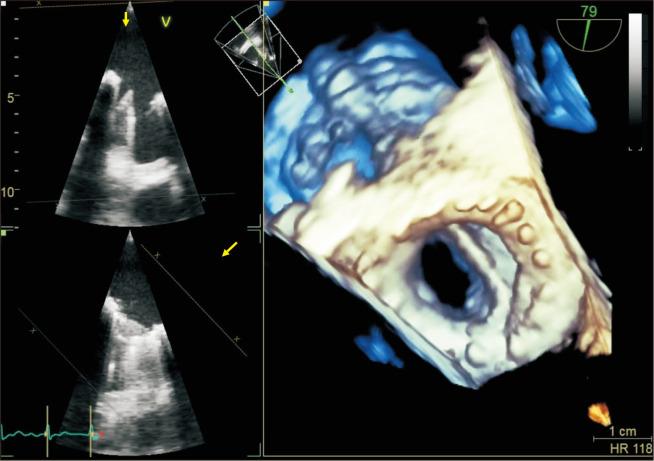

Fracture of prosthetic valve leaflets in the absence of traumatic injury is very rare. Leaflet fracture can cause acute pulmonary edema and cardiogenic shock and is potentially life-threatening, requiring emergency surgery. Thus, a leaflet fracture must be diagnosed quickly and accurately. We present the case of a 46-year-old man with CarboMedics prosthetic aortic and mitral valve replacements implanted 24 years previously. The patient presented at our emergency department with abrupt dyspnea and fever. We diagnosed severe mitral valve regurgitation with anterior leaflet fracture. The patient underwent venoarterial extracorporeal membrane oxygenation and delayed mitral valve replacement. The foreign body was removed step by step because the diagnosis was missed. Two pieces of broken leaflets were found in the left common iliac artery and left external iliac artery. The patient was treated successfully and remains asymptomatic 1 year following surgery.

在无创伤性损伤的情况下,人工瓣膜小叶骨折非常罕见。小叶骨折可导致急性肺水肿和心源性休克,有潜在生命危险,需要紧急手术。因此,必须快速准确地诊断小叶骨折。我们报告一例46岁男性病例,其24年前植入了CarboMedics人工主动脉瓣和二尖瓣。该患者因突发呼吸困难和发热就诊于我院急诊科。我们诊断为严重二尖瓣反流伴前叶骨折。患者接受了静脉-动脉体外膜肺氧合及延迟二尖瓣置换术。由于漏诊,异物被逐步取出。在左髂总动脉和左髂外动脉中发现了两片破碎的小叶。患者治疗成功,术后1年无症状。